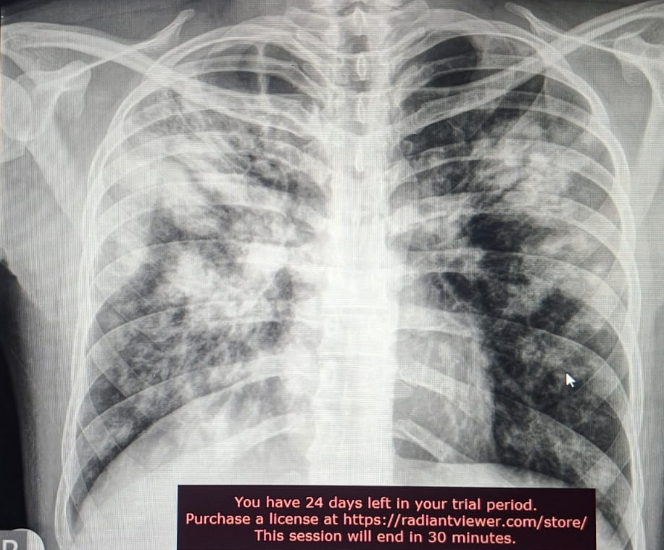

draurtecho Ene 26, 2026 No es gripe… es tuberculosis Si tenes síntomas respiratorios como: tos seca o productiva, asociada a malestar general, pérdida del apetito, fiebre, pérdida de peso, de más de 14 días, sin mejoría; debes buscar atención especializada. La siguiente radiografía es de tuberculosis activa No Comments InNeumología

draurtecho Dic 3, 2025 Tuberculosis y diabetes La tuberculosis pulmonar se puede presentar más frecuente, en las personas diabéticas. Si tenes fiebre o tos, o síntomas respiratorios, hay que buscar atención medica e iniciar a realizar estudios, como una radiografía de tórax. En la siguiente radiografía, se muestra una complicación de la tuberculosis pulmonar en un paciente diabético. No Comments InNeumología